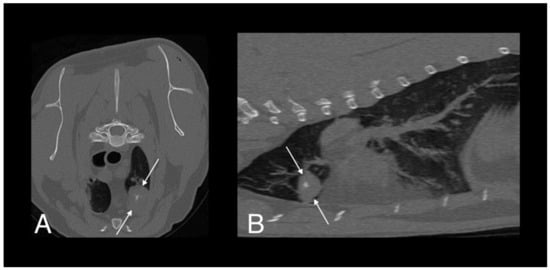

- Bennett, A.D.; Lalor, S.; Schwarz, T.; Gunn-Moore, D.A. Radiographic findings in cats with mycobacterial infections. J. Feline Med. Surg. 2011, 13, 718–724. [Google Scholar] [CrossRef] [PubMed]

- Major, A.; Holmes, A.; Warren-Smith, C.; Lalor, S.; Littler, R.; Schwarz, T.; Gunn-Moore, D. Computed tomographic findings in cats with mycobacterial infection. J. Feline Med. Surg. 2016, 18, 510–517. [Google Scholar] [CrossRef]

- Major, A.; O’Halloran, C.; Holmes, A.; Lalor, S.; Littler, R.; Spence, S.; Schwarz, T.; Gunn-Moore, D. Use of computed tomography imaging during long-term follow-up on nine feline tuberculosis cases. J. Feline Med. Surg. 2018, 20, 189–199. [Google Scholar] [CrossRef]